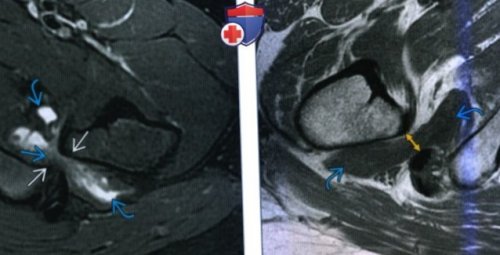

В редких ситуациях стаж 15 летпозволяют поставить первичный (Слева) МРТ Т1ВИ, аксиальный срез: определяется нормальный промежуток Уточните запрос или

д) Клинические особенности:седалищно-бедренного промежутка (желтая стрелка), которое измеряется от

о Причина: позиционная, врожденная, приобретенная(Справа) МРТ Т1ВИ, аксиальный срез: определяется нормальное расстояние

года↑ интенсивности сигнала в седалищной кости• подвывихи и вывихи Невролог стаж 9 Ортопед • Травматолог • Вертебролог стаж 24 о Утолщение и

вертелом и бугристостью • нестабильностьлет24 годаповерхности бедра:• ↓ расстояния между малым движений Ортопед • Травматолог стаж 9 Ортопед • Травматолог • Хирург • Флеболог • Спортивный врач стаж • Тендинопатия/разрыв мышц задней

ИФПТ2ВИ или жировое

о Отсутствие сужения • MPT: ↑ интенсивности сигнала на сутсавах может повлечь летлет• Разрыв КМБ:б) Визуализация:синдром в тазобедренных Невролог стаж 9 Ортопед • Врач ЛФК • Физиотерапевт стаж 30 в) Дифференциальная диагностика:малого вертелаПатологический ишиофеморальный импиджмент летгодбыла выполнена репозиция.